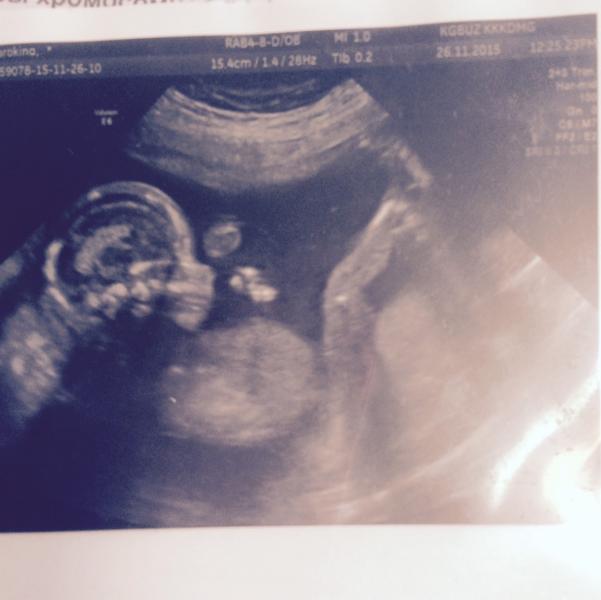

@darinakadi, мне в Красноярске делали, аппарат УЗИ там классный, конечно👍